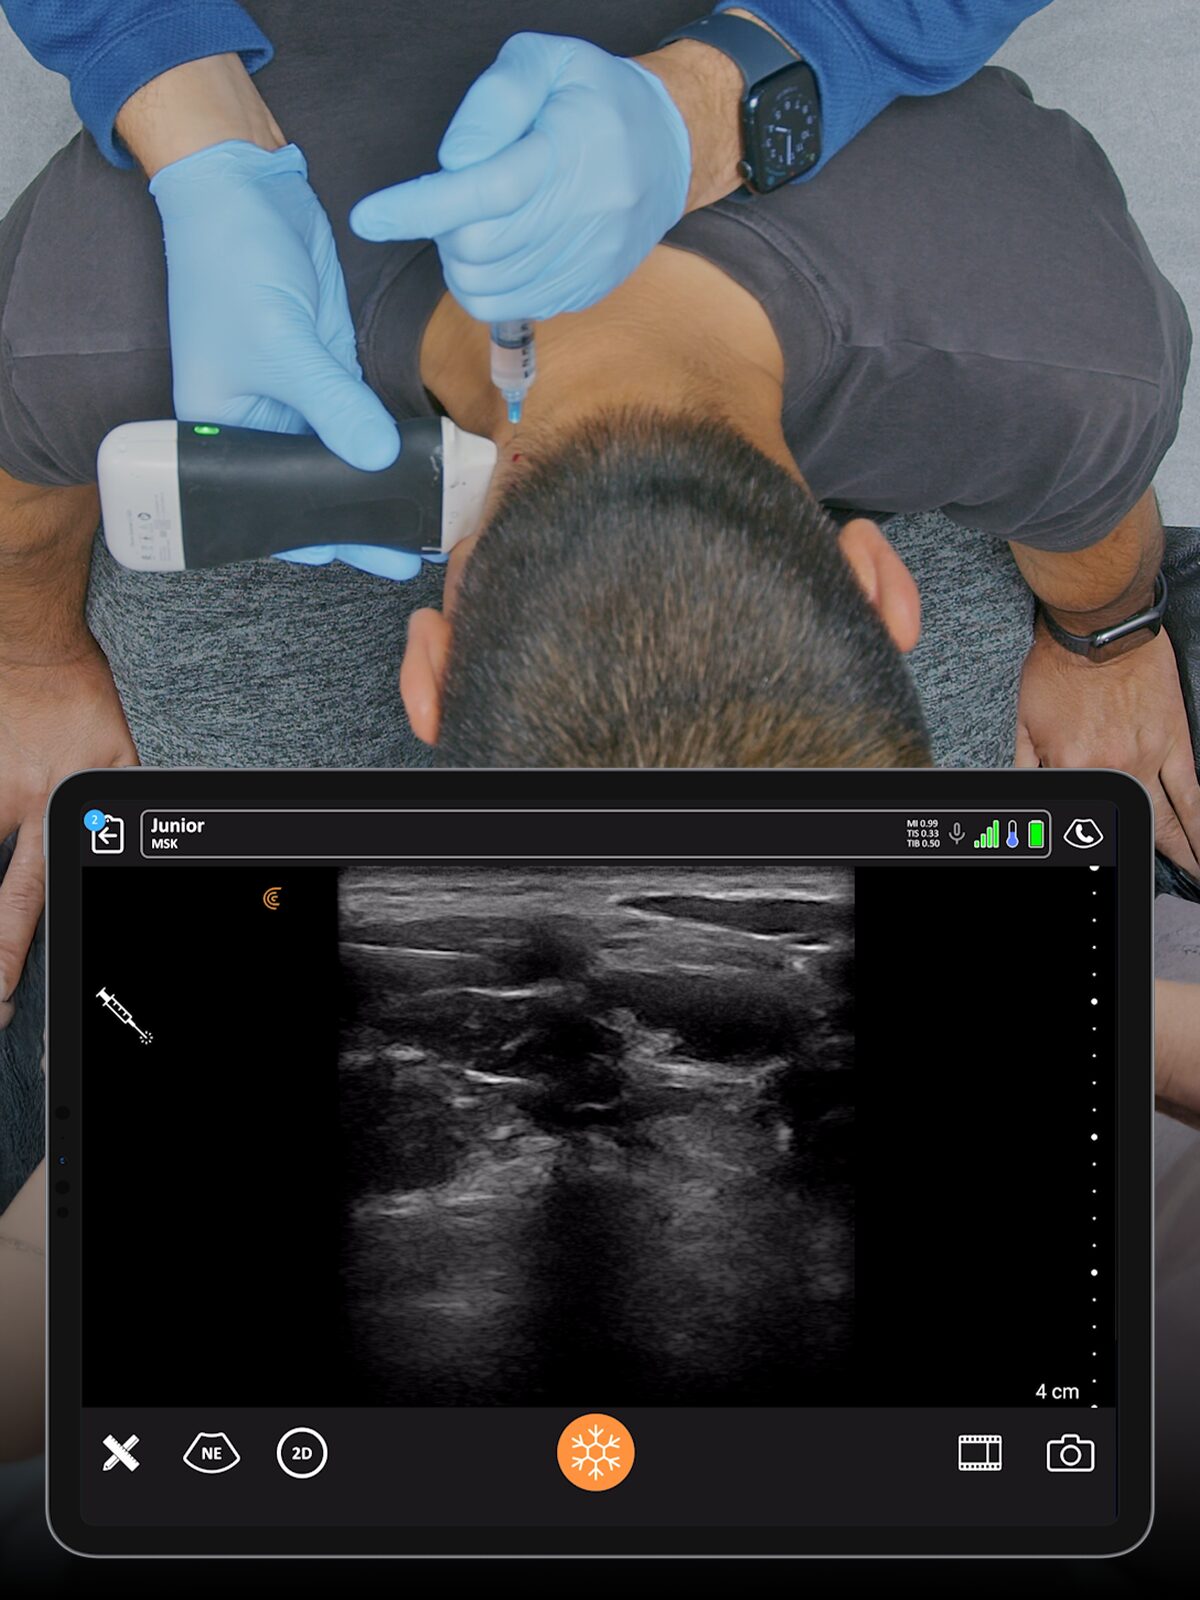

Get Athletes Back in Action – Faster.

Specialized presets and high resolution provide fast, accurate imaging for athletes’ needs.